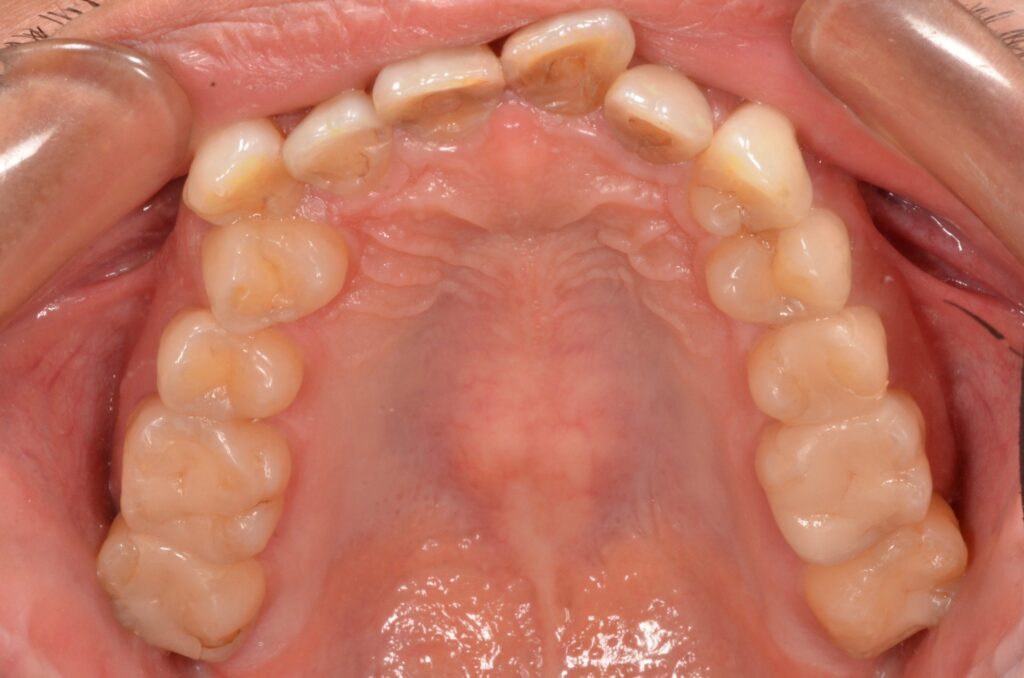

特に前歯に叢生が見受けられます。ワイヤー矯正であれば半年から一年で治療終了できそうですが、患者様のご要望でマウスピース治療となりました。

また、前歯4本は色も濃くプラスチックで補綴されていることもありセラミック治療となりました。